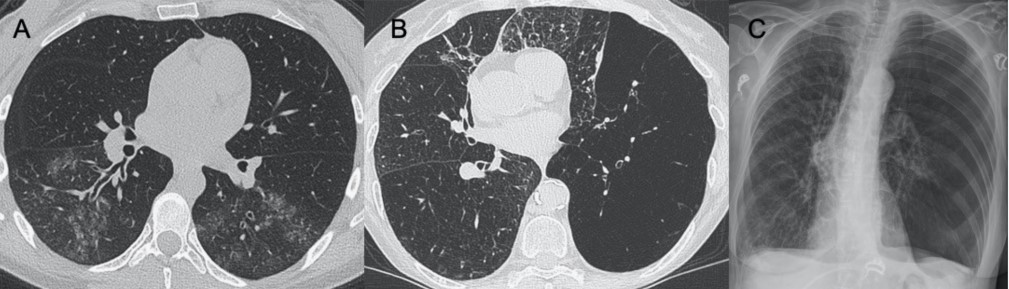

?腺病毒

● CXR:雙側(cè)和多灶性GGO,可表現(xiàn)為肺葉或節(jié)段性分布,與細(xì)菌性肺炎相似。出現(xiàn)并發(fā)癥時(shí),單側(cè)肺透亮過(guò)度和呼氣時(shí)空氣滯留(Swyer–James綜合征)。

● CT:雙側(cè)和多灶性GGO,可表現(xiàn)為肺葉或節(jié)段性分布,與細(xì)菌性肺炎相似。

圖5 腺病毒肺炎和Swyer–James綜合征。圖(A)顯示了一例急性腺病毒肺炎,具有典型的多灶性和大葉GGO,與細(xì)菌性肺炎相似。圖(B,C)顯示其導(dǎo)致的長(zhǎng)期后遺癥——Swyer–James綜合征的表現(xiàn)。